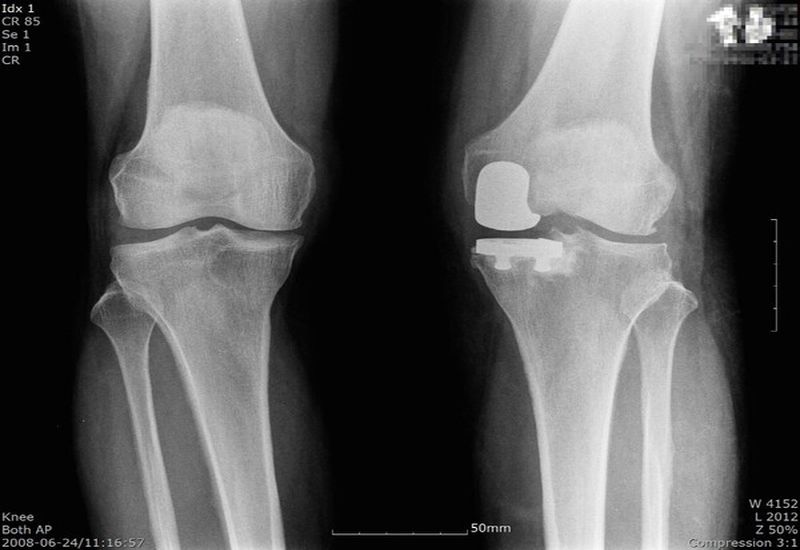

전문가들은 이른 나이에 퇴행성 관절염 말기에 달한 50~60대 환자들에게 가장 좋은 대안으로 ‘인공관절 부분치환술’을 주목하고 있다.

‘부분치환술’은 말 그대로 손상된 부분만 인공관절로 교체해주는 수술법으로, 자기관절을 보존하는데 이상적이다.

전체를 교체하는 전치환술에 비해 수술 부위가 5~7cm로 작고 회복이 빠르다. 입원기간 역시 짧고 일상이나 직장으로의 복귀가 빠르다는 장점이 있다.

그리고 무엇보다 자기관절을 보존하기 때문에 정상 관절과 비슷하게 무릎을 구부릴 수 있고, 계단을 오르고 내릴 시 전치환술 보다 편안함을 느낄 수 있다.

부분치환술 수명은 10~15년 정도로 보고되고 있는데 이후 재수술이 필요하다면 전치환술을 통해 관절 교체가 가능하다.

비교적 젊은 나이에는 부분치환술을 하고, 10~15년 후 전치환술을 한다면 남은 여생을 큰 통증 없이 보내며 삶의 질을 높일 수 있다.